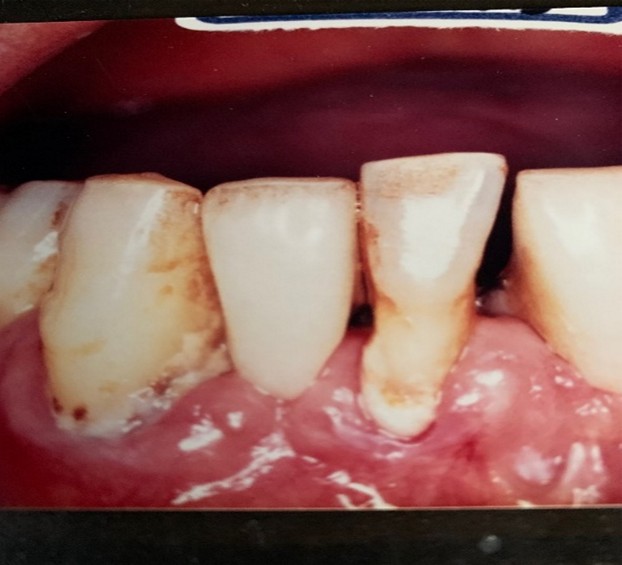

(歯の付け根に見えるプラーク。食べ物の残骸ではありません)

あの歯の白いねとねとのばい菌は、さわれば落ちます。